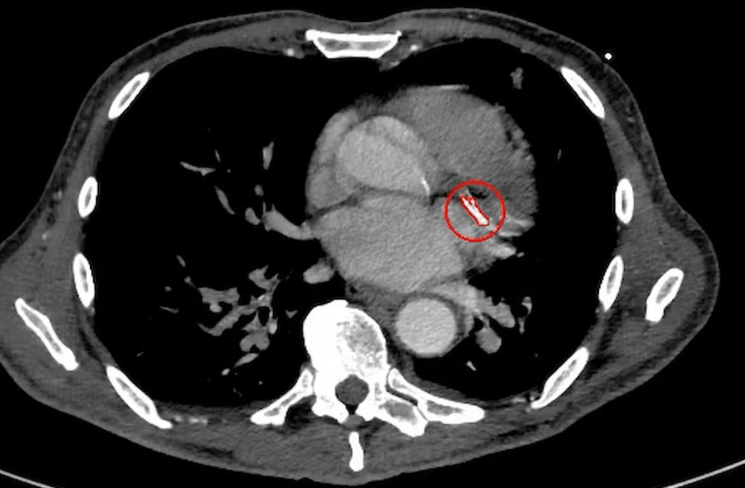

2026年《新英格兰医学杂志》发表的SMART-DECISION试验提供了新数据。这项韩国多中心随机试验招募2540名左心室射血分数至少40%、无心力衰竭的稳定患者,随机分配停用或继续β受体阻滞剂。主要终点为全因死亡、复发心肌梗死或心力衰竭住院。中位随访3.1年,停用组7.2%发生主要终点,继续组为9.0%,两组左心室射血分数和生活质量变化相似,停用后血压和心率适度增加但无显著临床后果。

试验结果支持与稳定患者讨论停药可能,尤其是出现副作用如疲劳、心动过缓或希望减轻药物负担者。但证据不适用于心力衰竭、左心室射血分数降低或需要心率控制的心律失常患者。指南机构表示将重新审视该群体长期使用,强调个体化选择的重要性。